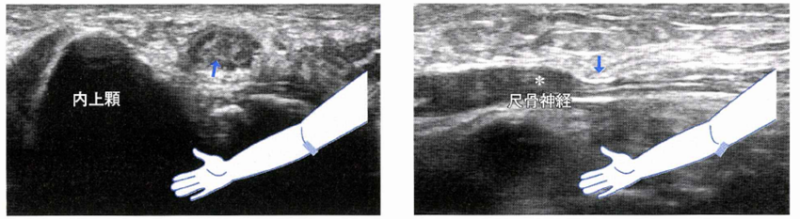

尺骨神経は腫大し,低エコーを呈している(→) オズホーンバンドで神経が圧迫され(→)、その中枢の腫大(*:偽神経腫)を認める

必ずしも、エコー上 偽腫瘍などの肥厚が認められるわけではありません。やはり実際の症状をみて、診断することが多いです。